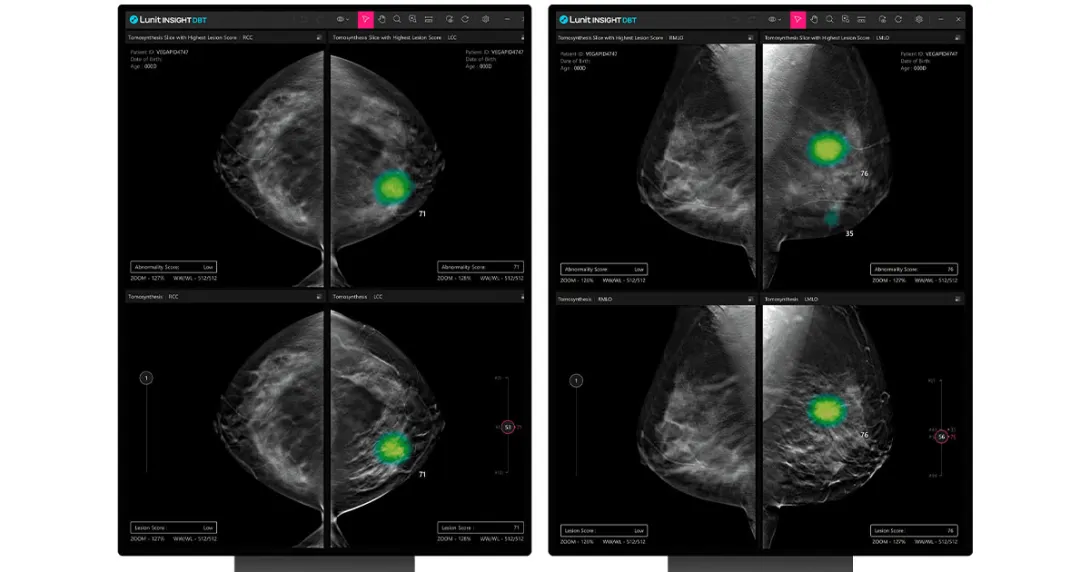

FDA clears Lunit breast cancer screening algorithm

Lunit, a provider of AI-powered solutions for cancer diagnostics and therapeutics, announced Tuesday that the U.S. Food and Drug Administration has cleared its 3D Breast Tomosynthesis algorithm to enter the U.S. breast screening market.

Lunit INSIGHT DBT analyzes 3D images to increase the accuracy of breast cancer diagnoses.